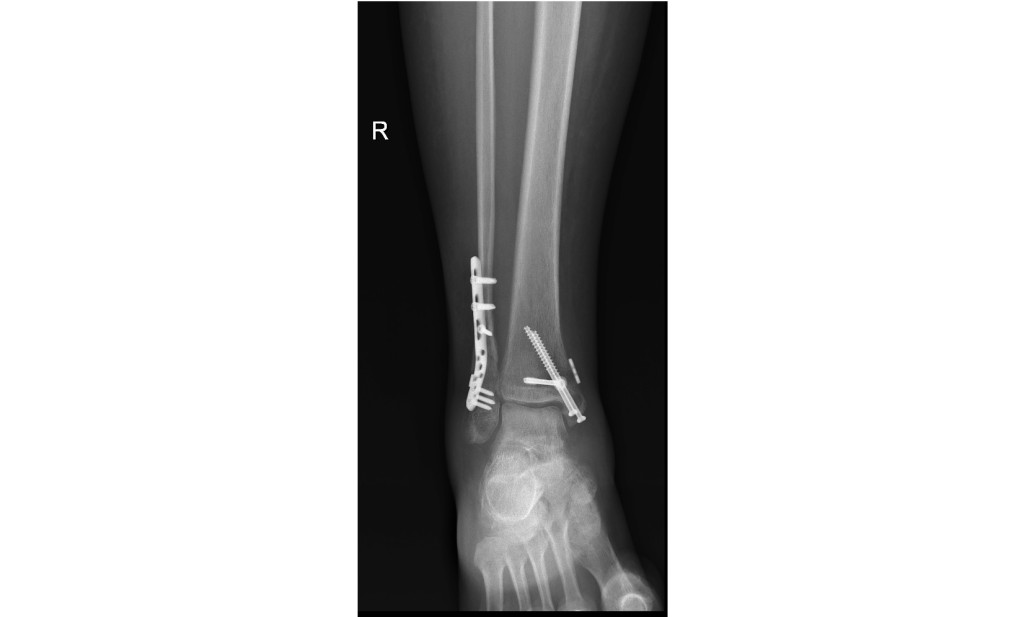

She has 9 screws, a self tensioning fixator and a 6" metal plate in her ankle.

Here's what my wife's ankle looks like: